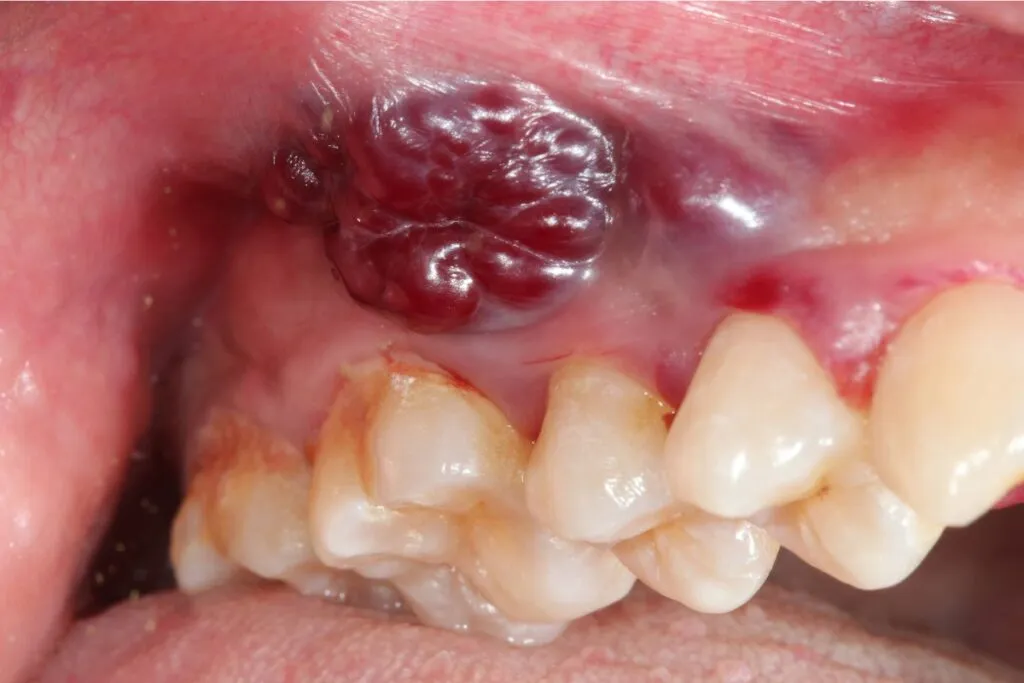

Guzek, zgrubienie, opuchlizna: dlaczego nie można ich ignorować?

Pojawienie się guzka, zgrubienia lub niewyjaśnionej opuchlizny na dziąśle, której wcześniej nie było, to kolejny sygnał, którego nie wolno ignorować. Nowotwór często manifestuje się jako masa tkankowa. Taka zmiana może być twarda w dotyku, nieregularna i początkowo bezbolesna. Niezależnie od jej wielkości czy towarzyszących objawów, każda nowo powstała masa w jamie ustnej wymaga natychmiastowej oceny medycznej, aby wykluczyć lub potwierdzić złośliwy charakter.